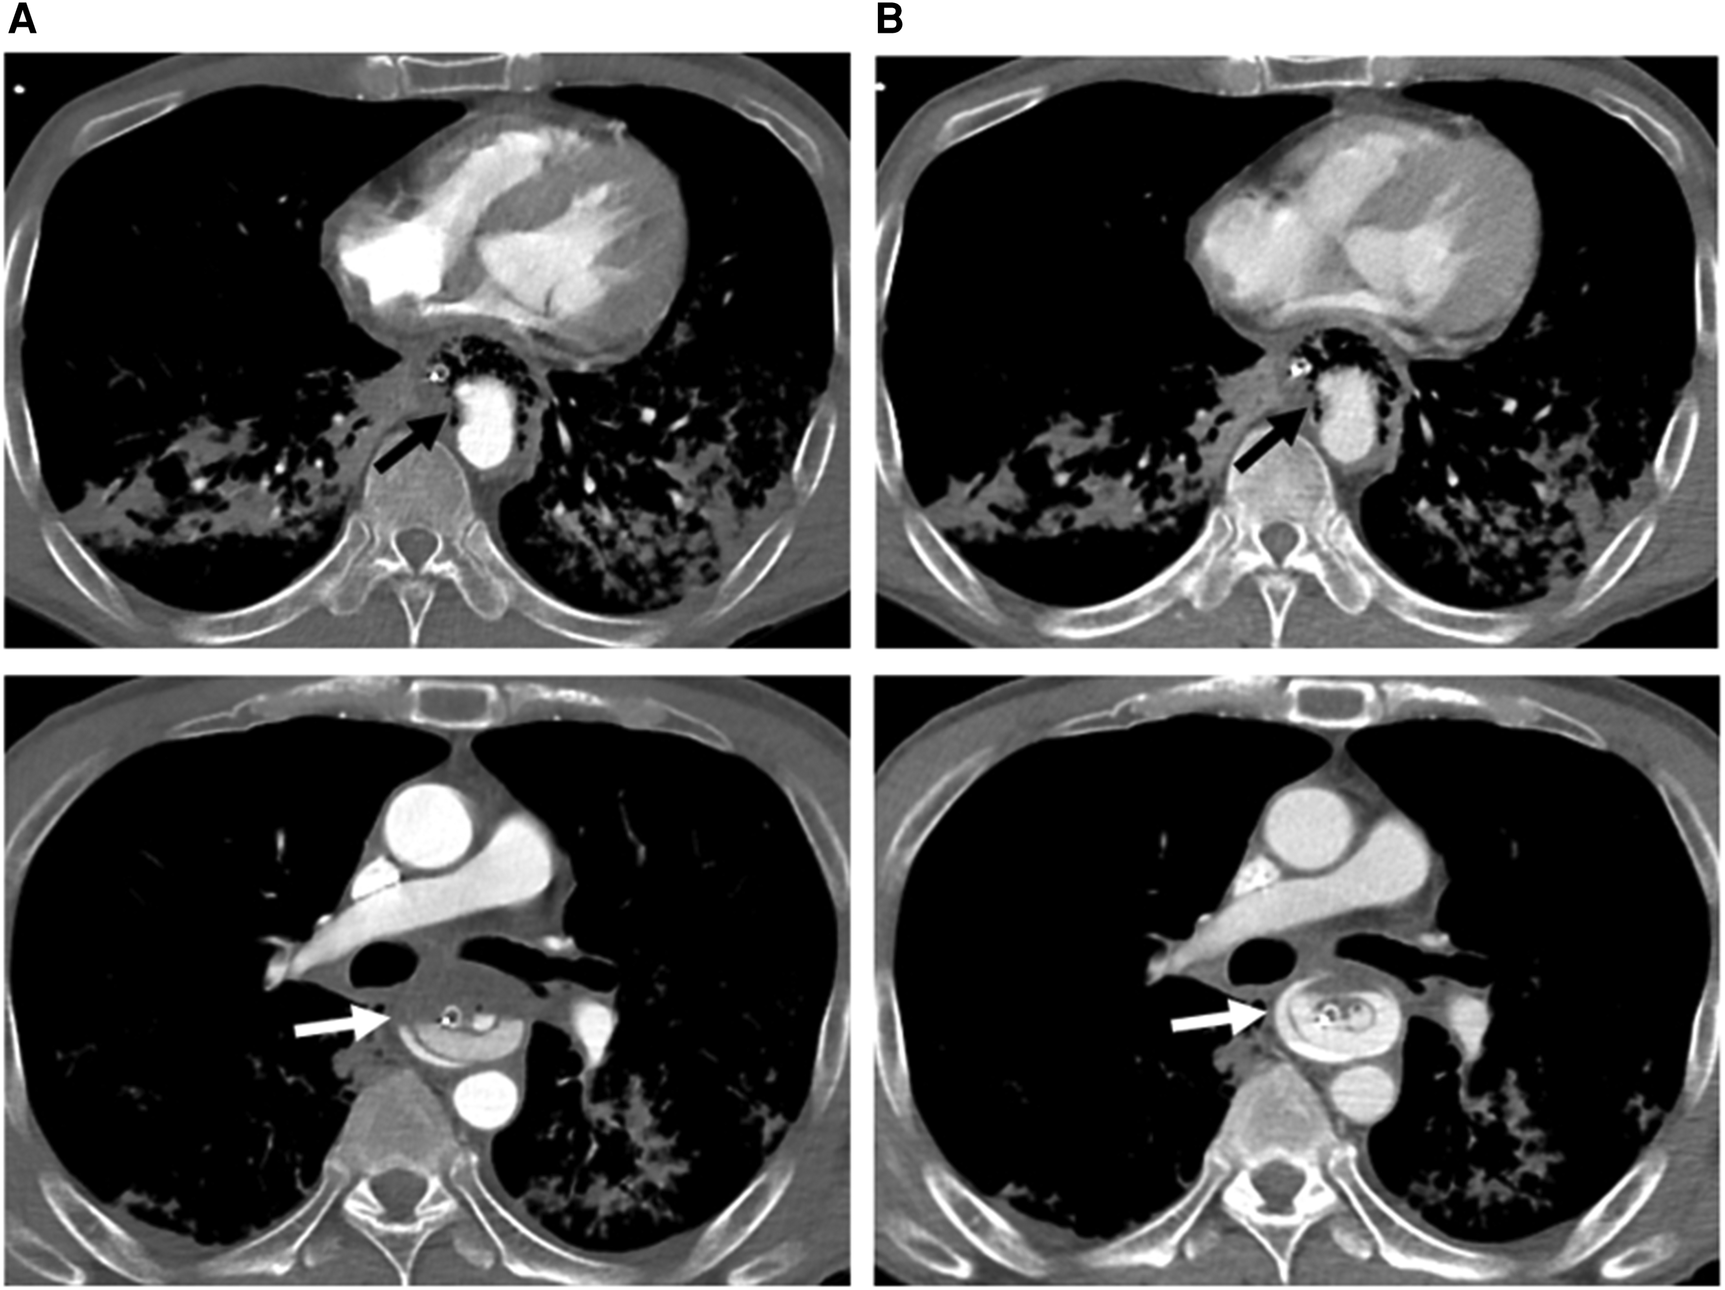

Figure 1. Axial computed tomography angiography of arterial (A) and venous (B) phases at two different levels below the carina, demonstrating a descending aortic pseudoaneurysm (black arrow) protruding into the esophagus (with a nasogastric tube in situ) through an aortoesophageal fistula (evidenced by direct communication of esophagus and aorta). There is a progressive increase in amount of contrast material (white arrow) in the esophagus, indicating rupture of the pseudoaneurysm and active bleeding.